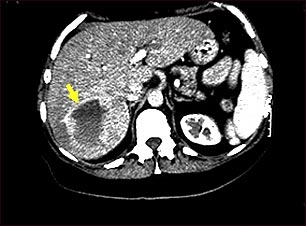

Esta TC abdominal superior muestra un tumor de un vaso sanguíneo (hemangioma) en el hígado.